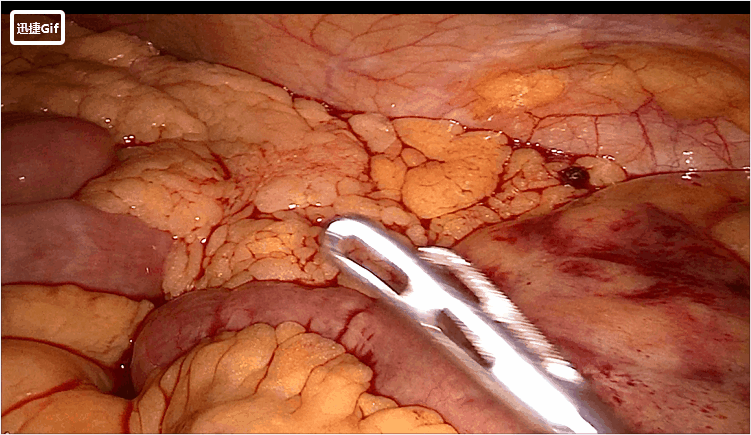

尤其是肠系膜相对肥厚的患者,此时游离的位置足够低,但肠系膜游离的长度不够长,即“瘦身”长度不够,外翻是翻到肛门外了,但是由于“瘦身”长度不够,凯图夹持组织过多,导致闭合困难,最后不得已还要将肠管再次送回腹腔再次游离。

原因:由于患者肥胖,腹腔充满大网膜和肠管,剩余空间不足,抵钉座隐藏在了小肠间隙之中,靠缺乏触觉感的腹腔镜器械寻找就好比大海捞针,甚是困难。